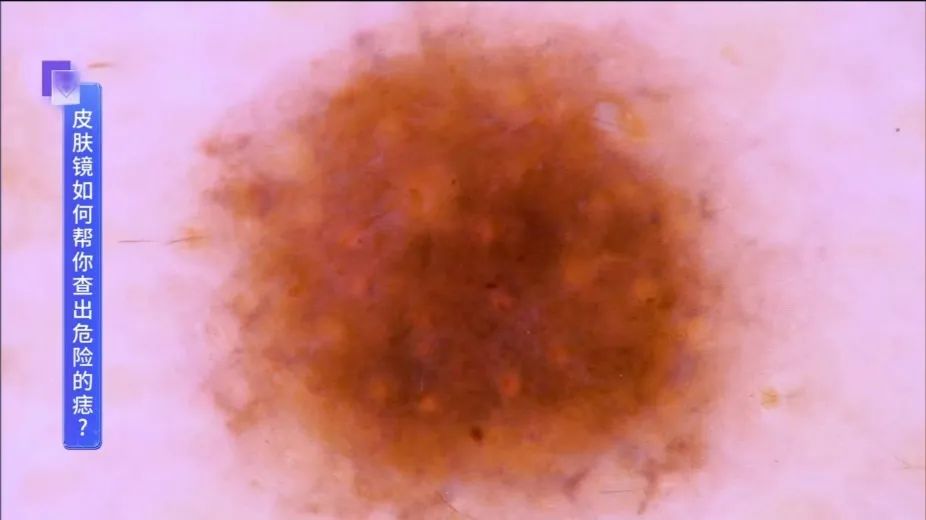

良性色素痣,多为常规色素分布。↓